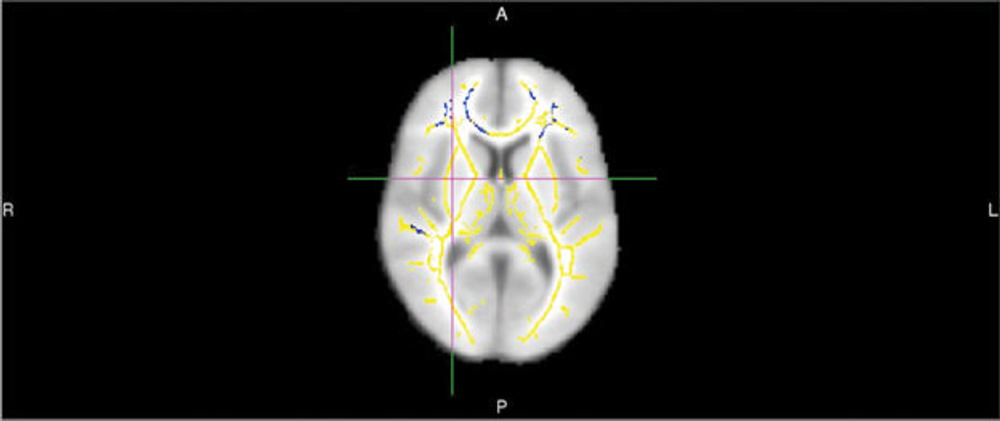

Figure 1. This image shows areas of reduced fractional anisotropy - a diffusion MR imaging marker of white matter damage - in 20 persons who develop Alzheimer's dementia compared to 20 who remain cognitively normal. These areas show up as blue-colored voxel overlaid onto a white matter skeleton (yellow colors) overlaid onto a standard template brain.

About half of the patients went on to develop Alzheimer’s disease, and DTI identified quantifiable differences in the brains of those patients. People who developed the disease had lower FA compared with those who didn’t, suggesting white matter damage. They also had statistically significant reductions in certain frontal white matter tracts.

“DTI performed very well compared to other clinical measures,” Dr. Raji said. “Using FA values and other associated global metrics of white matter integrity, we were able to achieve 89 percent accuracy in predicting who would go onto develop Alzheimer’s disease. The Mini-mental State Examination and APOE4 gene testing have accuracy rates of about 70 – 71 percent.”